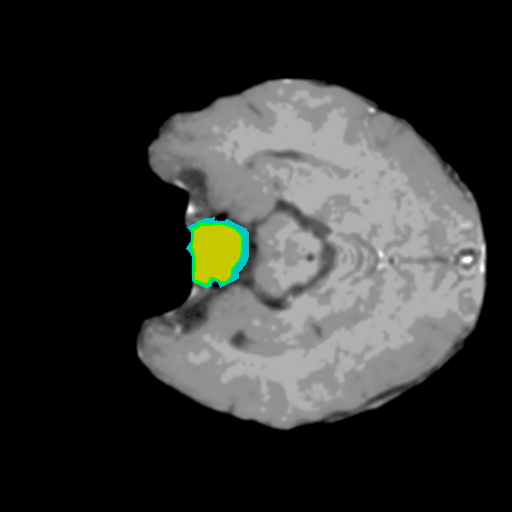

Extensive experiments have been performed in the current setup, and experimental outcomes are reported with the demonstration of numerical and statistical analyses using the proposed QFS-Net, QIS-Net [39], convolutional U-Net [18] and Residual U-Net (URes-Net) architectures [20]. The human expert segmented skull-tripped contrast enhanced DSC brain MR input image slices of size and ROIs are provided in Figure 5 as samples. The demonstration of QFS-Net segmented images followed by the essential post-processed outcome on the slice no. for class level with four distinct activation schemes () are shown in Figure 6. It is evident from the experimental data provided in Table LABEL:tab1 that the proposed QFS-Net performs optimally for the -connected quantum fuzzy pixel information heterogeneity assisted activation () with and gray scale set in comparison with other thresholding schemes and gray scale sets under the four evaluation parameters () [44]. The segmented tumors obtained using the proposed self-supervised procedure under class transition levels with four different thresholding schemes , , and are demonstrated in Figures 7- 8 for the class boundary sets and [39], respectively. The segmented images using the remaining two class boundary sets ( and ) [39] are provided in the supplementary materials section. The segmented ROIs describing the whole tumor region after the masking procedure using QIS-Net, U-Net and URes-Net are also reported in Figure 9.